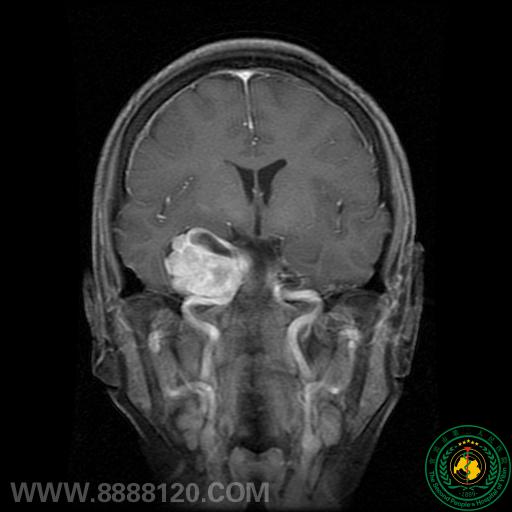

我科顺利独立开展全市首例经乙状窦-幕下联合入颅跨中后颅窝肿瘤切除术

我科顺利独立开展全市首例经乙状窦-幕下联合入颅跨中后颅窝肿瘤切除术7347